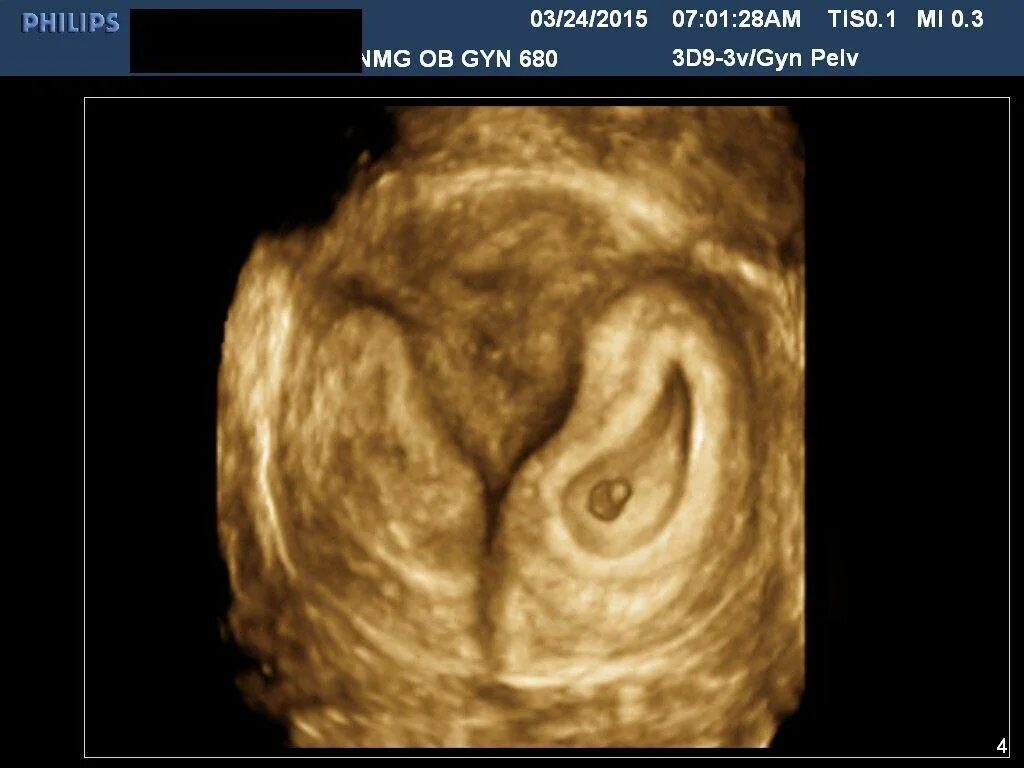

На какой неделе прикрепляется к матке